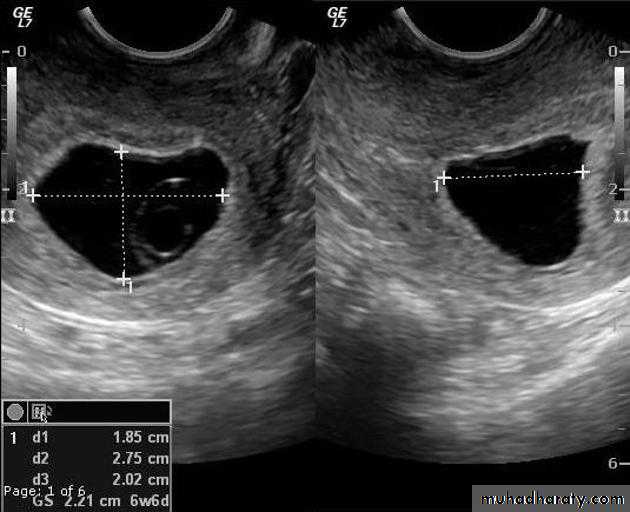

Anembryonic pregnancy is a form of a failed early pregnancy, where a gestational sac develops, but the embryo does not form. The term blighted ovum is synonymous with this, but is falling out of favour and is best avoided.

Radiographic features

Ultrasound

An anembryonic pregnancy may be diagnosed when there is no fetal pole identified on endovaginal scanning , and:

the size of the gestational sac is such that a fetal pole should be seen: MSD ≥25 mm on TVS (by RCOG criteria)